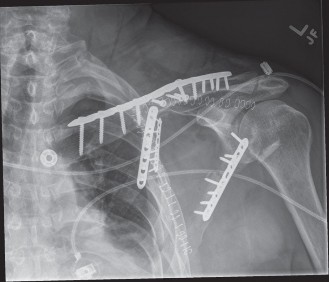

- Figure 1: Pre-operative CT scan with 3D reconstruction demonstrating a complex scapular body and neck fracture with significant displacement and angulation. Such detailed imaging is critical for accurate surgical planning and identifying the optimal approach.